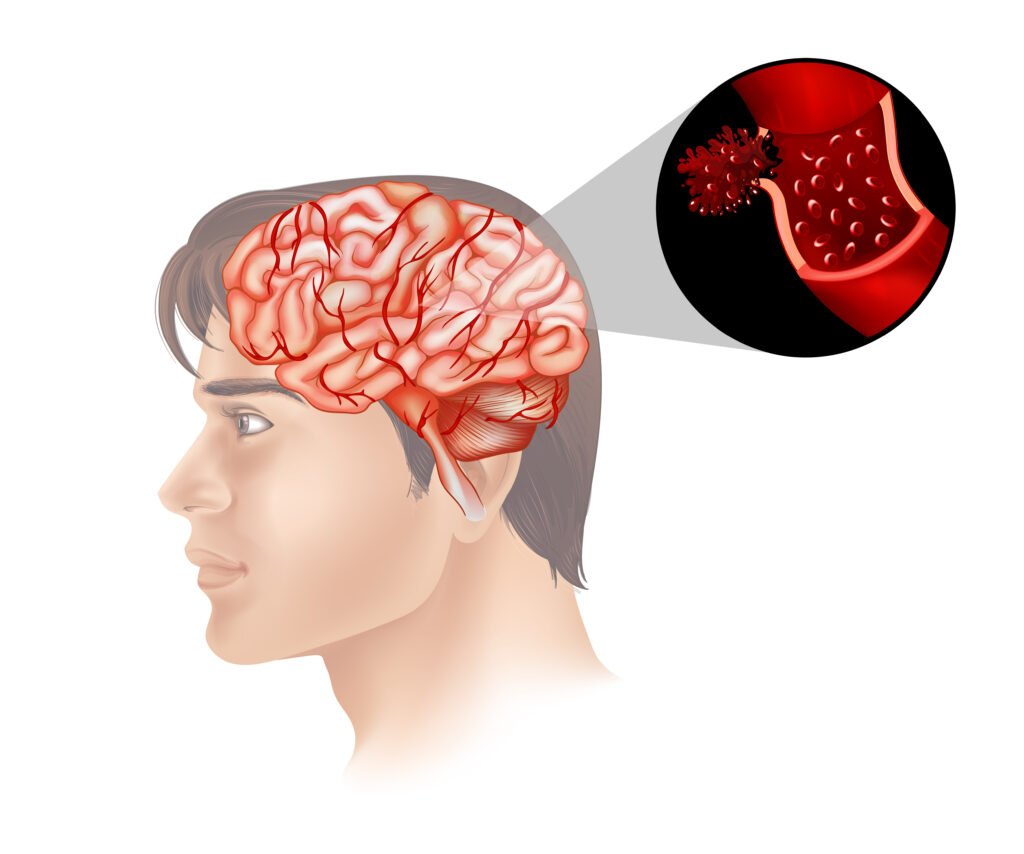

Metabolic encephalopathy is a consequence of disruption to the normal metabolic process, which is essential in mediating brain homeostasis and brain functioning. The brain depends upon unremitting provision of energy and chemical equilibrium in blood, such as glucose, electrolytes, oxygen and lack of poisonous processing products. Low blood sugar levels, excess or reduced sodium, liver damage, kidney impairment, or the buildup of toxins upset the cellular setting of the brain when they cause metabolic imbalances.

- Energy Failure: A lack of glucose or oxygen can result in an insufficiency of ATP production by neurons and glial cells, thereby impairing cellular functionality.

- Loss of Cellular Homeostasis: It leads to excitotoxic swelling of cells because of too many neurotransmitters and blocked ionic balances.

- Toxin Accumulation: A buildup of metabolic toxins (e.g., ammonia in liver failure) impedes neuronal dysfunction.

- The changes in Cerebral Blood Flow and Vascular Reactivity: It can also worsen brain impairments through impairing the delivery of oxygen and nutrients.

- Liver Failure (Hepatic Encephalopathy): Malfunction of the liver causes toxic substances such as ammonia to collect in the bloodstream. These toxins travel to the brain and interfere with neurotransmission, thus confusion, altered mental status, and coma.

- Kidney Failure (Uremic Encephalopathy): Reduced kidney functioning causes accumulation of uremic toxins and electrolytic imbalances. They cause brain metabolism impairment and neuron functioning, leading to cognitive impairment and encephalopathy.